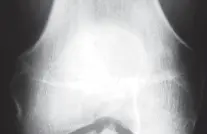

* الأشعة السينية (X-rays):

* الصور الأمامية الخلفية (AP) والجانبية (Lateral): تُظهر تآكل الغضروف وتضيق المسافة المفصلية.

* الصور الخلفية الأمامية المثنية (PA flexed): تُعد حاسمة لتقييم الحجرة الخلفية للركبة بشكل أفضل.

* صور الرضفة الفخذية (Sunrise/Patellofemoral views): لتقييم صحة مفصل الرضفة الفخذية.

* صور الأشعة السينية الطويلة للطرف السفلي (Full-length standing radiographs): من الورك إلى الكاحل، لتقييم المحاذاة الكلية للساق وتحليل أي تشوهات في المحور.